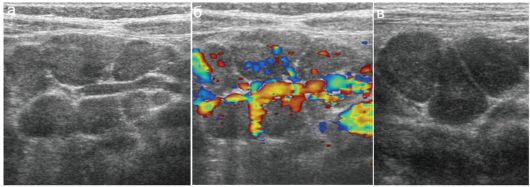

Мезентериальные лимфатические узлы: УЗИ и диагностика

Раздел: Лаборатория идей